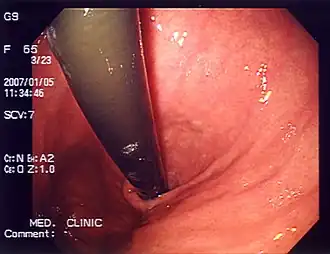

Endoscopy photo of a peptic ulcer

Peptic ulcer, a differential diagnosis for heartburn,[8] in the gastric antrum

The differential diagnosis, a process used by healthcare professionals to help differentiate a diagnosis from other similar disorders,[9] for heartburn includes motility disorders such as achalasia and gastroparesis; peptic ulcers; functional dyspepsia; angina;[8] eosinophilic esophagitis; coronary artery disease; functional heartburn;[10] peristalsis; acid reflux; inflammation of the esophagus (esophagitis), stomach (gastritis), pancreas (pancreatitis), gallbladder (cholecystitis), and duodenum (duodenitis); esophageal cancer; ischemic pain; hiatal hernia; biliary colic; stomach cancer; gallstones; pancreatic cancer; duodenal ulcer; and mesenteric adenitis.[4] Heartburn can also be caused by certain medications such as nonsteroidal anti‐inflammatory drugs, corticosteroids, tetracycline antibiotics, bisphosphonates, calcium‐channel blockers, nitrates, tricyclic antidepressants, and anticholinergics.[4]

Endoscopic photo of the stomach

An endoscopy may be used to help find the cause of heartburn.[23]

Endoscopy is a method used to detect abnormalities in the esophageal lining such as erosive esophagitis and Barrett's esophagus. Biopsies taken during an endoscopy can help assess for other conditions linked to heartburn, such as eosinophilic and lymphocytic esophagitis.[14] The esophageal 24-hour pH test or the multichannel intraluminal impedance-pH test is often performed in those with refractory heartburn who have undergone an endoscopy. High-resolution esophageal manometry (HREM) is the standard test for diagnosing esophageal motor disorders. It helps rule out major motility issues in those with persistent heartburn who have normal endoscopy and pH testing. Motility disorders include achalasia, esophagogastric junction outflow obstruction, diffuse esophageal spasm, jackhammer esophagus, and absent contractility. HREM can also distinguish GERD from conditions like rumination and supra-gastric belching. In some cases, gastric scintigraphy may be used to detect gastroparesis.[24]